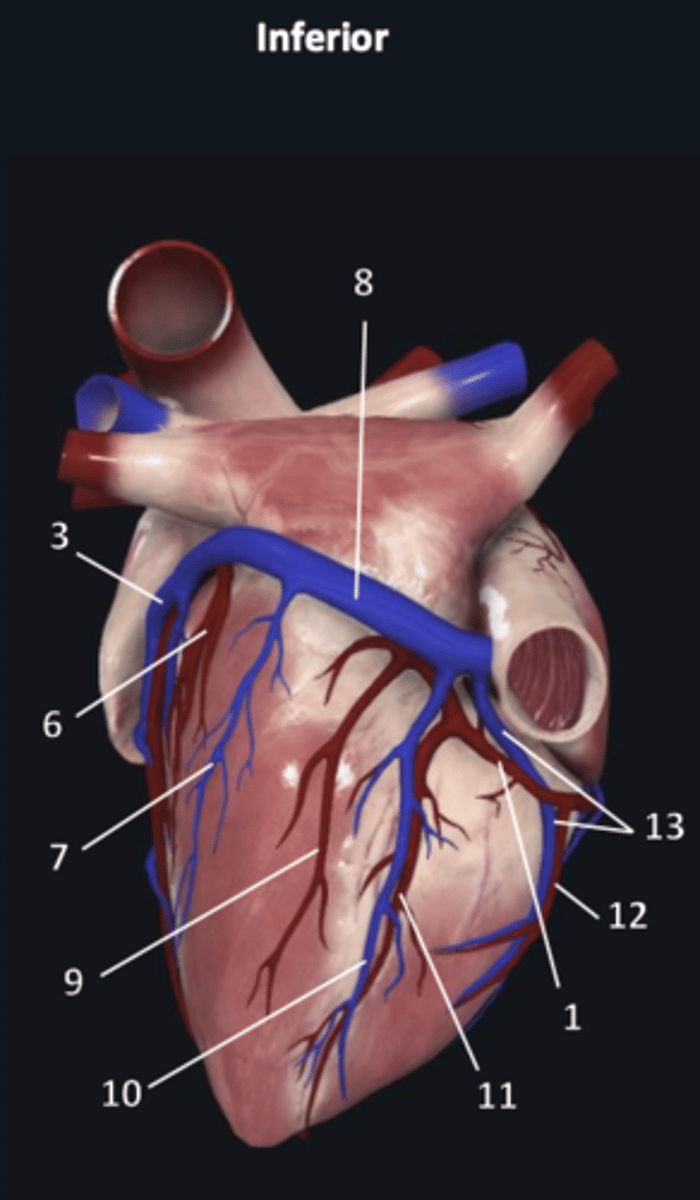

right coronary artery

1 (red)

great cardiac vein

3

posterior left ventricular artery

6

posterior vein of left ventricle

7

coronary sinus

8

right posterolateral artery

9

middle cardiac vein

10

posterior interventricular artery

11

right marginal artery

12

small cardiac vein

13